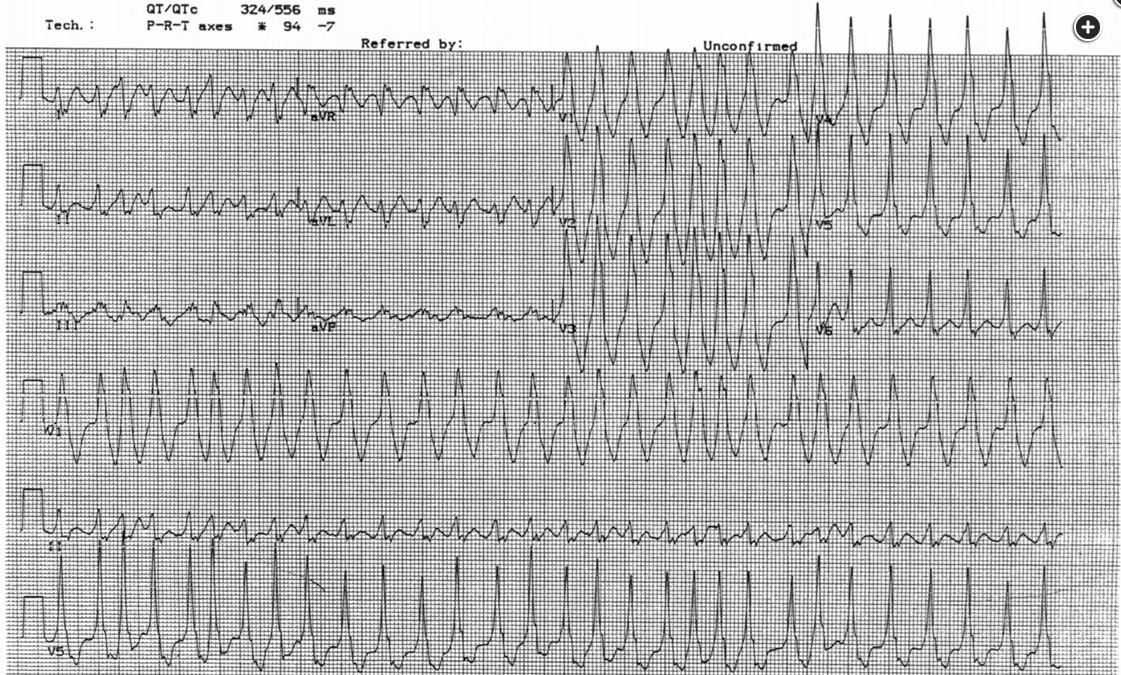

The rhythm is atrial fibrillation—it is irregularly irregular without discernible P waves. Some of the intervals are very short—the interval between the second and third beat is about 220 milliseconds; if sustained, this would correspond to a heart rate of 273/min. The QRS complex is wide in some beats, narrower in others, and in fact, differs from beat to beat. This combination of features makes the diagnosis of Wolff-Parkinson-White (WPW) syndrome with atrial fibrillation.

This patient has developed an acute tachyarrhythmia. At first glance, the QRS complex appears wide. However, closer inspection shows that the tachyarrhythmia is irregularly irregular.

Furthermore, the widths of the QRS are also irregular and vary between beats (best seen in the six-lead rhythm strip or lead V4 of the 12-lead ECG).

These three criteria, namely wide complex tachyarrhythmia, irregularly irregular rhythm, and varying widths of the QRS complexes, should prompt consideration of preexcited atrial fibrillation or atrial fibrillation in a patient with an accessory conduction pathway. This is also called preexcitation syndrome or Wolff-Parkinson-White syndrome. Patients with preexcitation syndrome have an accessory conduction pathway that directly connects the atria with the ventricles and bypasses the atrioventricular (AV) node. If conduction occurs through this accessory pathway, the ventricles are activated sooner than when the impulse travels through the AV node. This activation, which is referred to as preexcitation, results in the classic ECG findings of shortened PR interval and widened QRS complex due to a delta wave (red arrows in Figure 3).

A 28-year-old man with stage IIC testicular seminoma is being treated with bleomycin, etoposide, and cisplatin chemotherapy. During his third cycle, a rapid response is called to his room for tachycardia. Vital signs include a temperature of 37°C, heart rate of 180/min, BP of 111/72 mm Hg, and respiratory rate of 22/min. A 12-lead ECG (Figure 1) and six-lead rhythm strip (Figure 2) are obtained.